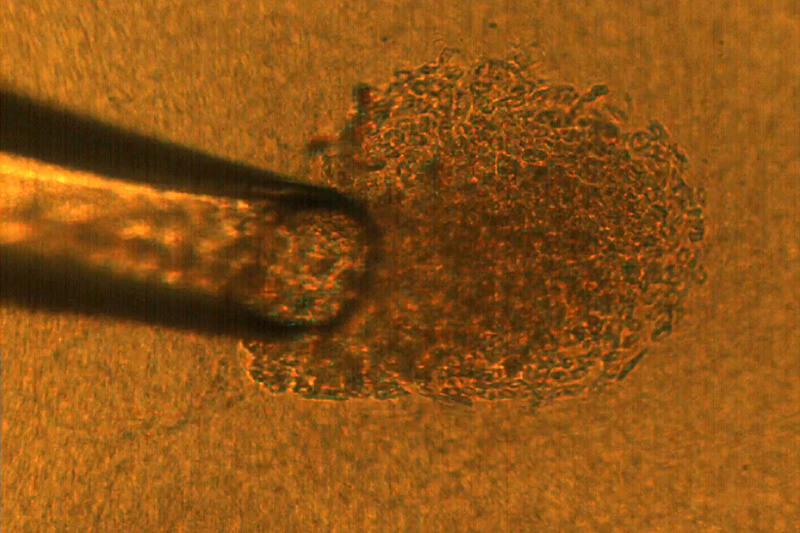

microscopic pipette capturing cancer cell

3D cell culture method points to personalized cancer therapies

Each cancer patient’s tumors have cells that look and act differently, making it difficult for scientists to determine treatments based on tumors grown from generic cell cultures in the lab. Now, thanks to a new 3D cell culture technique developed by Purdue researchers, it may be possible to personalize treatment by understanding the contributions of different cell types in a tumor to the cancer’s behavior.